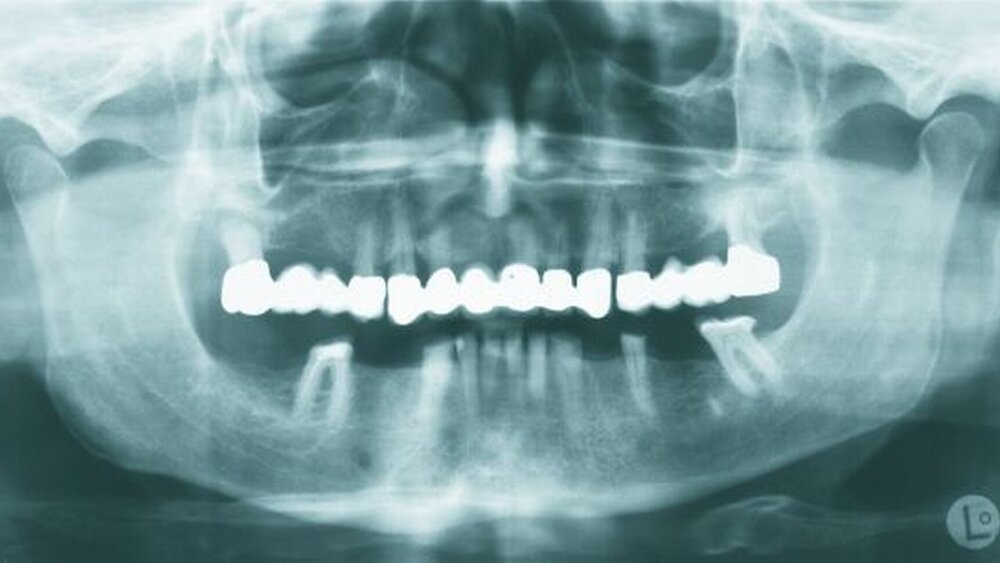

Auf dem vor Anfertigung des Zahnersatzes angefertigten OPG sowie den angefertigten Zahnfilmen der regiones 17 und 27 waren generalisierte horizontale Knochenverluste im Bereich aller verbliebenen Zähne erkennbar. Die Zähne 17 und 27 wiesen zudem vertikale Knocheneinbrüche auf. Eine radiologische Furkationsbeteiligung ließ sich in beiden Fällen nachweisen. Der Zahn 47 war wurzelkanalgefüllt.

Obwohl der Zahn 47 eine radiologisch nicht vollständig bis zum radiologischen Apex reichende Wurzelfüllung aufwies, wurde auf eine Revision der Wurzelfüllung aufgrund einer seit mehr als 15 Jahren bestehenden Beschwerdefreiheit des Patienten und vollständiger Symptomlosigkeit des Zahnes verzichtet [Peak et al., 1994]. Der Patient wurde über diese Sachverhalte ausführlich aufgeklärt und erklärte sich mit dem Belassen der Wurzelfüllung einverstanden.